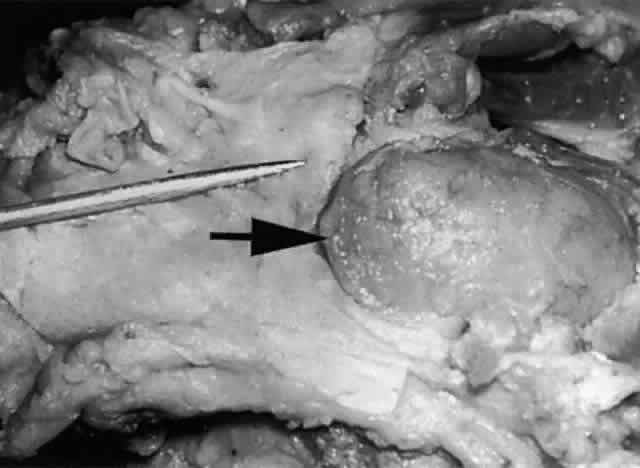

The main lacrimal gland resides in the superotemporal orbit, partially within a shallow bony fossa in the lateral angular process of the frontal bone (fossa glandula lacrimalis). The gland is situated between the eyeball below and the curved orbital wall above, giving it a somewhat compressed and curved shape. It may extend inferiorly to the lateral canthal tendon. The lateral horn of the levator aponeurosis crosses the gland anteriorly, separating it into a larger superior or orbital lobe and a smaller inferior or palpebral lobe (Fig. 2). The division is incomplete because the larger orbital lobe is connected to the smaller palpebral lobe posteriorly by a bridge of glandular tissue, draining tubules, and Müller's muscle, which is attached to the underside of the levator muscle and aponeurosis. The lacrimal gland is surrounded by fibrous tissue that is attached superiorly to the periosteum of the frontal bone and inferiorly to the orbital portion of the zygomatic bone.1

Fig. 2. With the roof and lateral wall of the left orbit removed, this cadaver dissection demonstrates the orbital lobe (black arrow) and the palpebral lobe (white arrow) separated by the lateral horn of the levator aponeurosis (pointer).